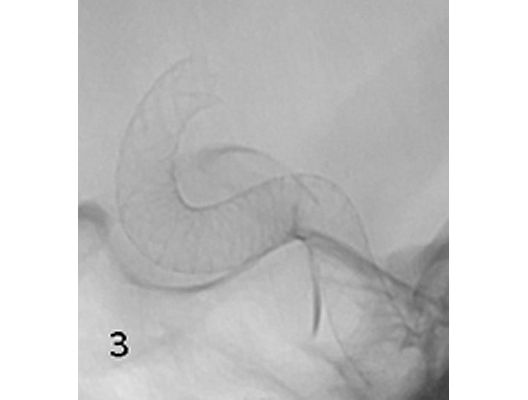

Aneurysmen an der Gefäßen des Gehirns können in vielen Fällen minimalinvasiv durch einen Zugang durch das Gefäßsystem, zumeist von der Leiste aus behandelt werden (sog. Endovaskuläre Therapie). Dabei gibt es z.B. die Möglichkeit ein Aneurysma durch Einbringung von Platinspiralen zu verschließen (sog. Coiling). Auch für komplexe Aneurysmen stehen inzwischen verschiedene endovaskuläre Methoden zur Verfügung.

Das Beispiel zeigt die angiographischen Bilder einer Patientin, bei der es zu einer Sehstörung gekommen war. Die Ursache war ein großes Aneurysma der Halsschlagader an der Schädelbasis (Bild 1). Bild 2 zeigt die Lage des Aneurysmas hinter dem Auge. Durch den Druck des Aneurysmas auf den Sehnerv war es zu der Sehstörung gekommen. Die Patientin wurde mit einer speziellen Gefäßprothese versorgt, welche über eine Punktion der Leistenarterie in die Halsschlagader eingesetzt wurde (Bild 3). Bei der Kontrolle nach 6 Monaten zeigte sich ein vollständiger Verschluss des Aneurysmas (Bild 4). Die Sehstörung hatte sich vollständig zurückgebildet.